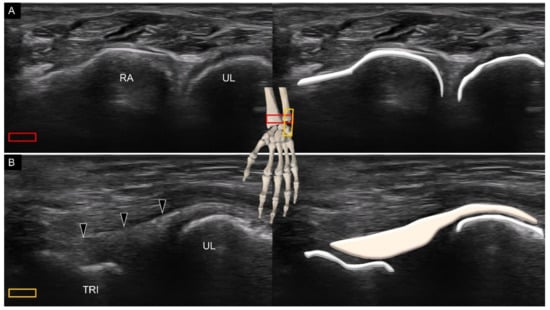

2. Sonoanatomy of Carpal Bones

3.1. Attachment to the Capitate

5. Sonoanatomy of Dorsal Extrinsic Carpal Ligaments

Attachment to the Triquetrum